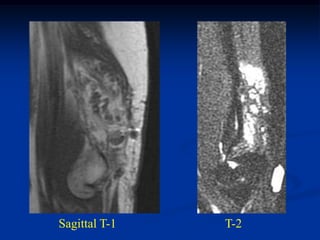

CLASSIC     Case #285         Sagittal T-1 MRI

67 year female with myxoid liposarcoma knee

Sagittal T-2 MRI

Axial T-2 MRI